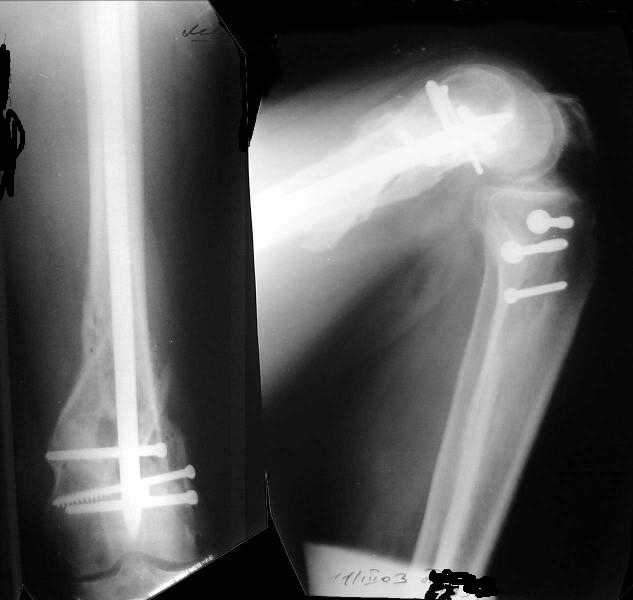

Отправитель: Alexander Chelnokov 27 Декабрь 2003, 21:34

Sorry but I've just prepared postop images - attached. A solid 13 mm nail was used. A few degrees of recurvation appears to be which i missed on image intensifier. I'm still uncertain about

advantages/disadvantages of ante/retrograde nailing for such fractures.

Отправитель: V.M.Iyer 27 Декабрь 2003, 21:36

The fixation as you have done is excellent. The locking screws on either side of the # are so apart. When we put in a supracondylar nail thro a keyhole incison in the knee, the locking bolts will be nearer the # and will be more stable allowing him to bear wt early. That was the reason the supracondylar nail was innovated. The locking is done by jig and no freehand method saving time.